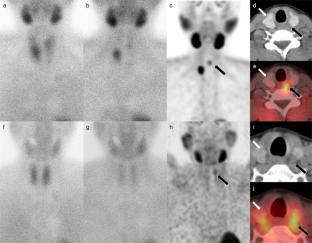

Fig. 1